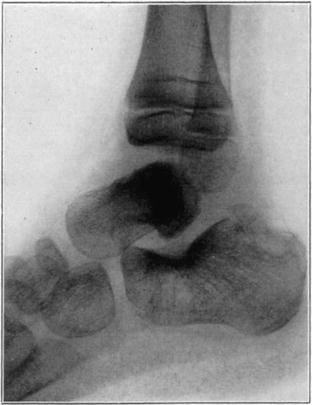

Case 2. Seventy-four days after fracture of neck of astragalus, posterior dislocation of body, and reduction by operation. Body necrotic and retained normal density. Atrophy of disuse of other bones. Bony union of fracture.

Case 2. One hundred and sixty days after fracture. Body slightly reduced in density near fracture due to invasion from neck.

Case 3. Fresh fracture of neck of astragalus and chip off superior and posterior portion of os calcis.

Case 3. Two hundred and seventy-four days after injury. Fracture of astragalus united. Superior and posterior part of body broken down and irregular while remaining portion dense and transformed. Indicative of necrosis of body with secondary changes.

Case 3. Eighteen months after injury, showing a defective but gradually reforming articular portion of the body of the astragalus.

The blood supply of the astragalus is derived mainly from a branch of the arteria dorsalis pedis which traverses the sinus tarsi lateral to the neck and breaks up to enter the bone near the junction of the neck and body along the lateral and inferior surfaces. There are very small branches entering the bone mesially and posteriorly at points of ligamentous and capsular attachments. Apparently when there is a fracture along the junction of body and neck the important vessels to the body are interrupted and there may be insufficient circulation through the remaining vessels, so that aseptic necrosis of a large part or all of the fragment follows. It is evident from the partial collapse which occurred in Case 3 that when necrosis of the body is diagnosed, the limb should be protected from weight-bearing for at least several months,—until union, revascularization, and transformation of necrotic area has been largely brought about. It seems probable that some of the bad results that have been reported in fracture of the neck of the astragalus, either united or ununited, have been due to overlooked aseptic necrosis of the body.